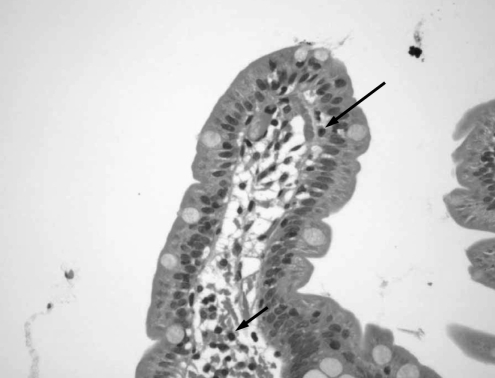

Six months later, as the patient continued to complain of abdominal pain, bloating, nausea and diarrhea, further studies were performed to exclude organic causes. Stool examination and abdominal ultrasound results were normal. In March 2000, an upper GI endoscopy with duodenal biopsies was performed to rule out CD. Duodenal biopsies showed normal mucosa with isolated subepithelial and lamina propria lymphocytes (Figure 1). A small bowel meal study showed no abnormality suggestive of Crohn’s disease. One month later, she presented with low serum urea concentrations, low vitamin B12, folate and ferritin levels, as well as a low lymphocyte count. Other results including erythrocyte sedimentation rate, C-reactive protein, thyroid stimulating hormone and serum immunoglobulin (Ig) A, IgG and IgE concentrations were normal. Because her lactose hydrogen breath test was positive, she was diagnosed with postinfective IBS and secondary lactose deficiency, and was treated with a lactose-free diet. Her vitamin deficiencies were treated with parenteral vitamin B12, oral folate and oral iron.

Figure 1).

First duodenal biopsy. Duodenal section showing normal villous structure. Isolated subepithelial (long arrow) and lamina propria (short arrow) lymphocytes were observed